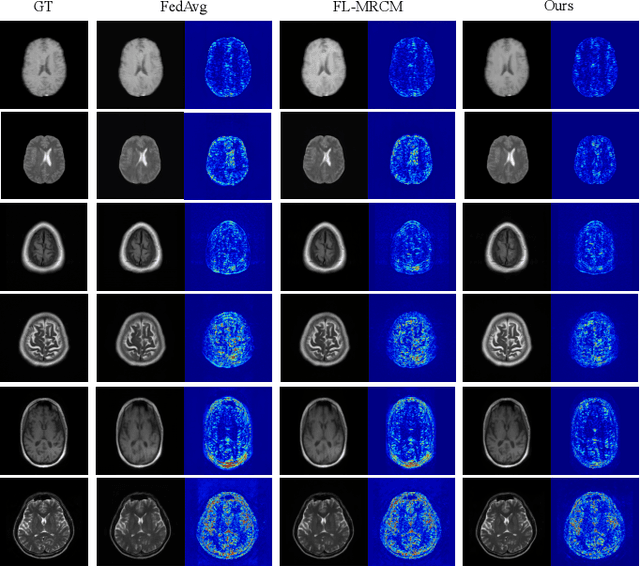

Abstract:Federated Learning (FL) is a machine learning paradigm where many local nodes collaboratively train a central model while keeping the training data decentralized. This is particularly relevant for clinical applications since patient data are usually not allowed to be transferred out of medical facilities, leading to the need for FL. Existing FL methods typically share model parameters or employ co-distillation to address the issue of unbalanced data distribution. However, they also require numerous rounds of synchronized communication and, more importantly, suffer from a privacy leakage risk. We propose a privacy-preserving FL framework leveraging unlabeled public data for one-way offline knowledge distillation in this work. The central model is learned from local knowledge via ensemble attention distillation. Our technique uses decentralized and heterogeneous local data like existing FL approaches, but more importantly, it significantly reduces the risk of privacy leakage. We demonstrate that our method achieves very competitive performance with more robust privacy preservation based on extensive experiments on image classification, segmentation, and reconstruction tasks.